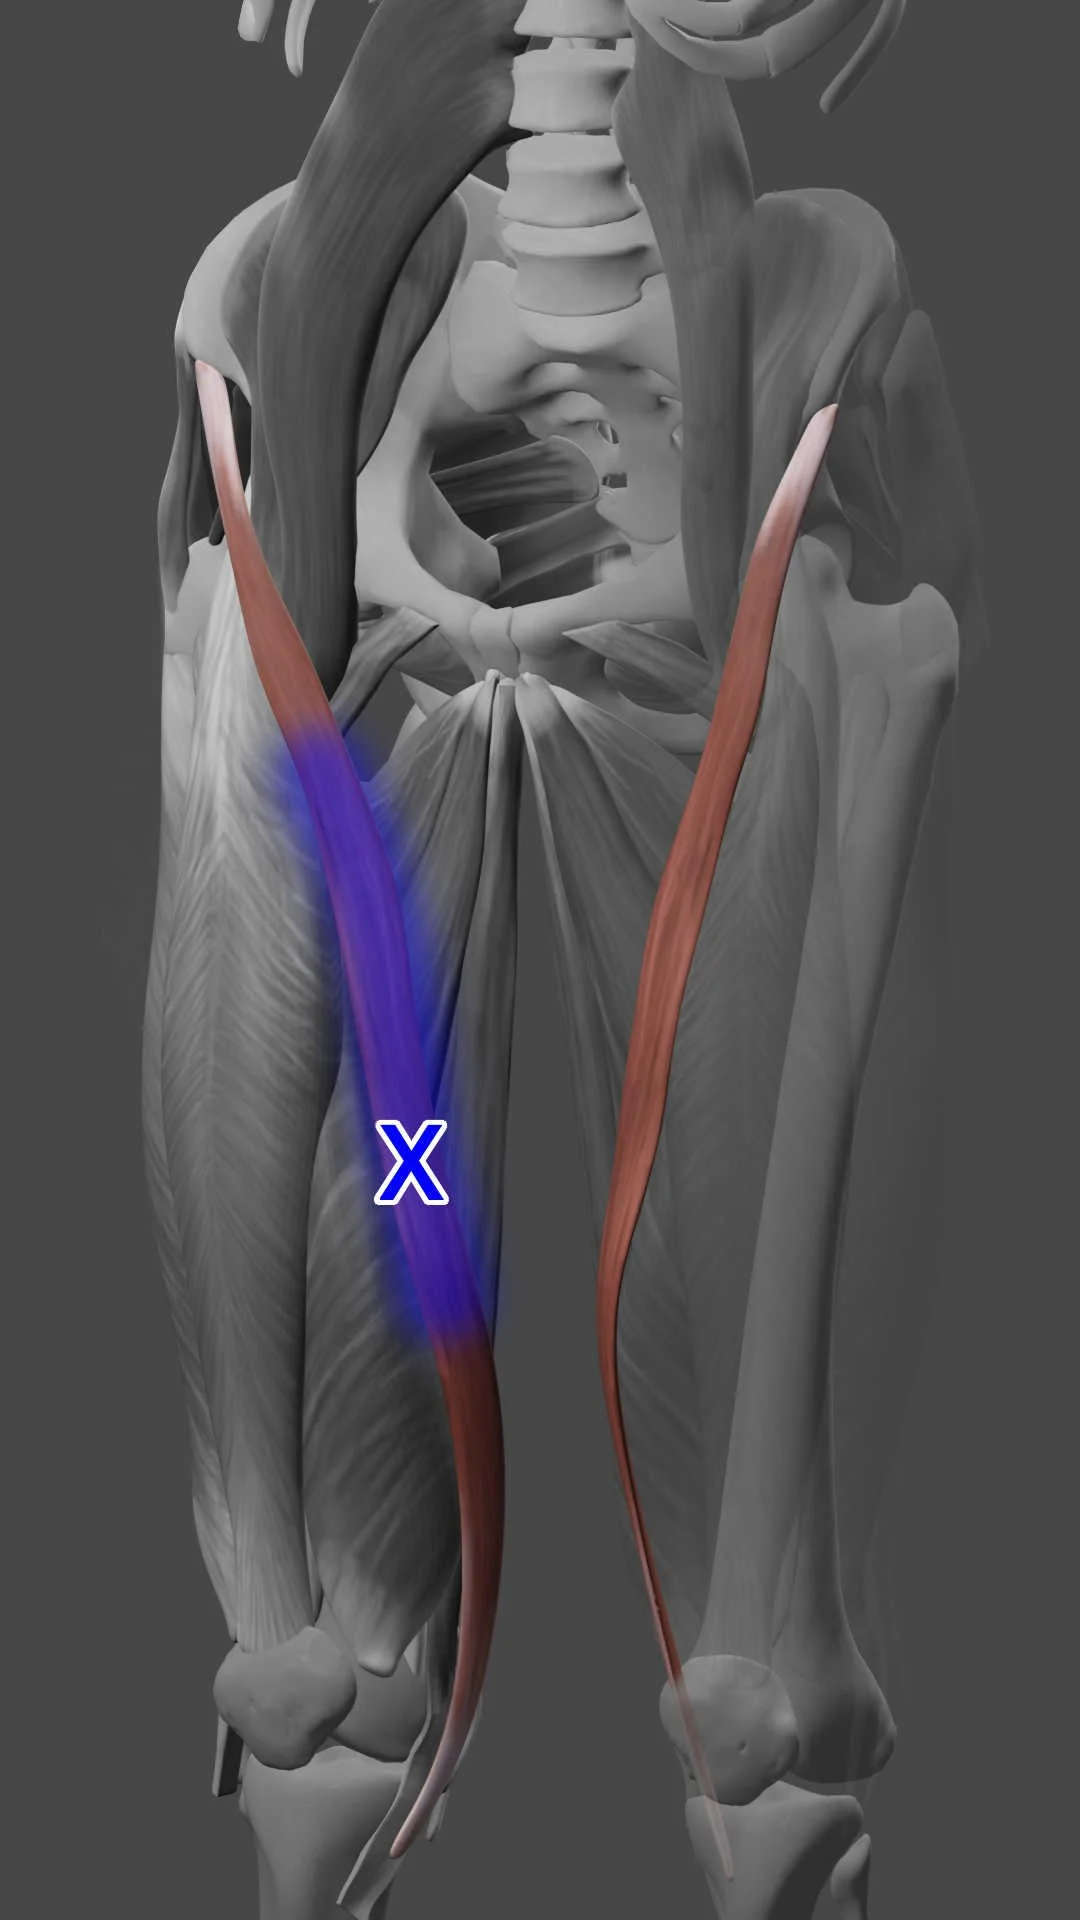

How does the sartorius muscle function during activities like getting in and out of a car?

what does sartorius muscle do Informational

- Why is the sartorius muscle sometimes referred to as the "tailor's muscle"?

- What is the length-tension relationship of the sartorius muscle?

- What are the potential benefits and risks of a sartorius muscle transfer?

- What type of muscle tissue is the sartorius muscle composed of?

- How does the force generated by the sartorius muscle vary with muscle length?

- How is sartorius muscle spasticity managed?

- Can the sartorius muscle affect the patellar tracking?

- Can swelling affect the sartorius muscle?

- Can the sartorius muscle be involved in shin splints?